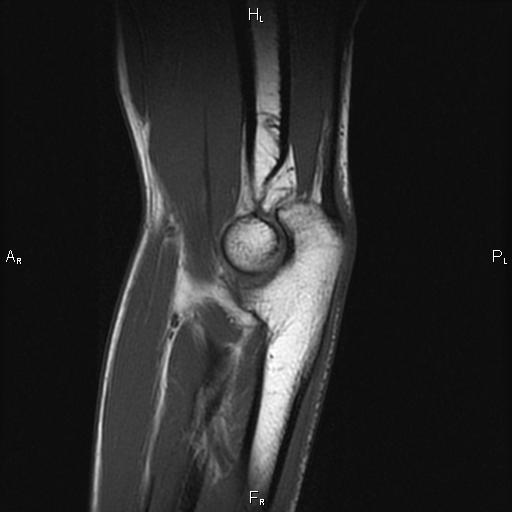

Как применяют МРТ для исследования локтевого сустава

Если рассматривать верхнюю конечность как функциональный орган, возможность движений придают ей плечевой, локтевой и кистевой или лучезастный суставы, а также суставы самой кисти, соединяющие пястье с фалангами и фаланги между собой.

Каждый из них играет свою важную роль в функционировании руки, однако уделим в данной статье особое внимание локтевому сочленению, как промежуточному в звене "плечо-предплечье".

В случае травматизма или поражения локтевого сустава различными заболеваниями, последний признан специалистами наиболее капризной структурой для реабилитации. Поэтому даже блестяще выполненная операция или консервативно сросшиеся кости дистального отдела плечевой кости или проксимального отдела костей предплечья не гарантируют полноценного функционирования конечности.

Для локтевого сочленения принципиально важное значение имеет ранняя диагностика любого патологического состояния в любом из его элементов, начиная от костно-суставного до сумочно-связочного и мышечно-сухожильного аппаратов. Вовремя нераспознанные, недолеченные патологические состояния или пролонгирование сроков иммобилизации сустава и отсутствие ранней функции в нем, благоволит интенсивным рубцовоспаечным процессам, плохо поддающимся восстановлению.

Поэтому метод МРТ, как наиболее информативный современный метод исследования локтевого сустава, должен стоять в начале перечня диагностических процедур.

Что показывает МРТ локтевого сустава

- Опухолевидные образования костных и окружающих мягких тканей

- Абсцессы, инфекционные процессы

- Бурсит (скопление жидкости в суставной сумке)

- Синовиит (воспаление сухожильных оболочек)

- Травмы сумочно-связочного аппарата, сухожилий, суставных поверхностей с поражением хрящевой ткани

- Повреждения околосуставных мышц

- Артриты / артрозы

- Повреждение срединного и лучевого нервов

- Эпикондиоиты (воспаление надмыщелков плечевой кости)

- Остеонекроз (аваскулярный некроз)

- Диагностика скрытых переломов или переломов неясного происхождения